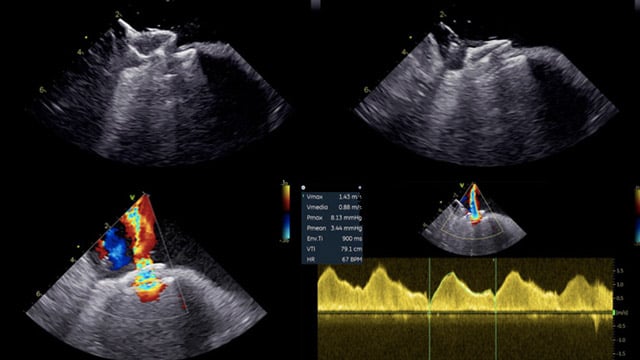

Paravalvular leak closure: challenges and percutaneous solutions

21 May 2025 – From EuroPCR 2025

This session addresses the challenges and percutaneous techniques for paravalvular leak closure following valve replacement. Through complex case studies, it explores managing unexpected anatomical defects, dealing with failed closure attempts, and strategies in malpositioned valves, providing practical guidance for successful intervention in difficult scenarios.